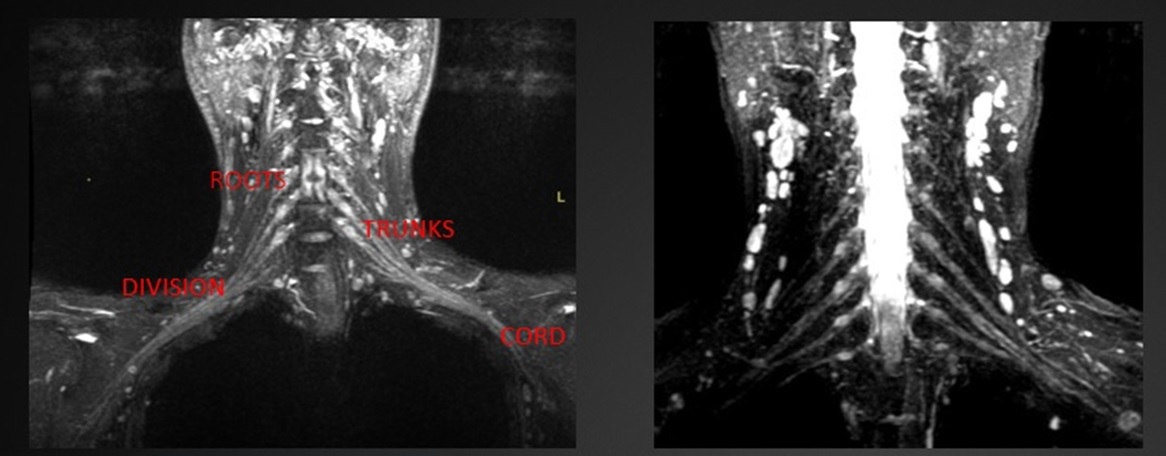

Background

This study explored whether Myelin Water Imaging could detect myelin injury in Anti-NMDA receptor autoimmune encephalitis (NMDAr-AIE), where traditional neuroimaging is often normal. Myelin Water Fraction (MWF) quantifies myelin content by distinguishing myelin sheath water from other brain water compartments.

Methods

Adult participants with confirmed NMDAr-AIE diagnoses and healthy controls (HC) underwent 3T brain MRI (Magnetic Resonance Imaging) including MWF mapping. Participants were recruited after discharge from the hospital. Mean MWF was calculated for 4 white matter regions of interest (ROI). MHI (Myelin heterogeneity Index) was calculated by dividing the MWF standard deviation by the mean MWF. Patient demographics, clinical assessments, treatment, and outcomes were collected.

Results

Fig. 1 Myelin Water Imaging of two selected patients

Screenshot 2025 06 01 at 12.05.23 pm

Myelin Water Imaging showed no myelin pathology in five NMDAr-AIE patients, with MWF and MHI values comparable to HC, suggesting that myelin pathways are relatively preserved post-recovery from AIE. Moving forward, we aim to continue recruiting healthy controls, patients post-recovery and those experiencing active disease to determine if there are any MWF abnormalities throughout the disease course. Future studies are needed to assess MWF changes in other antibody-mediated encephalitides.